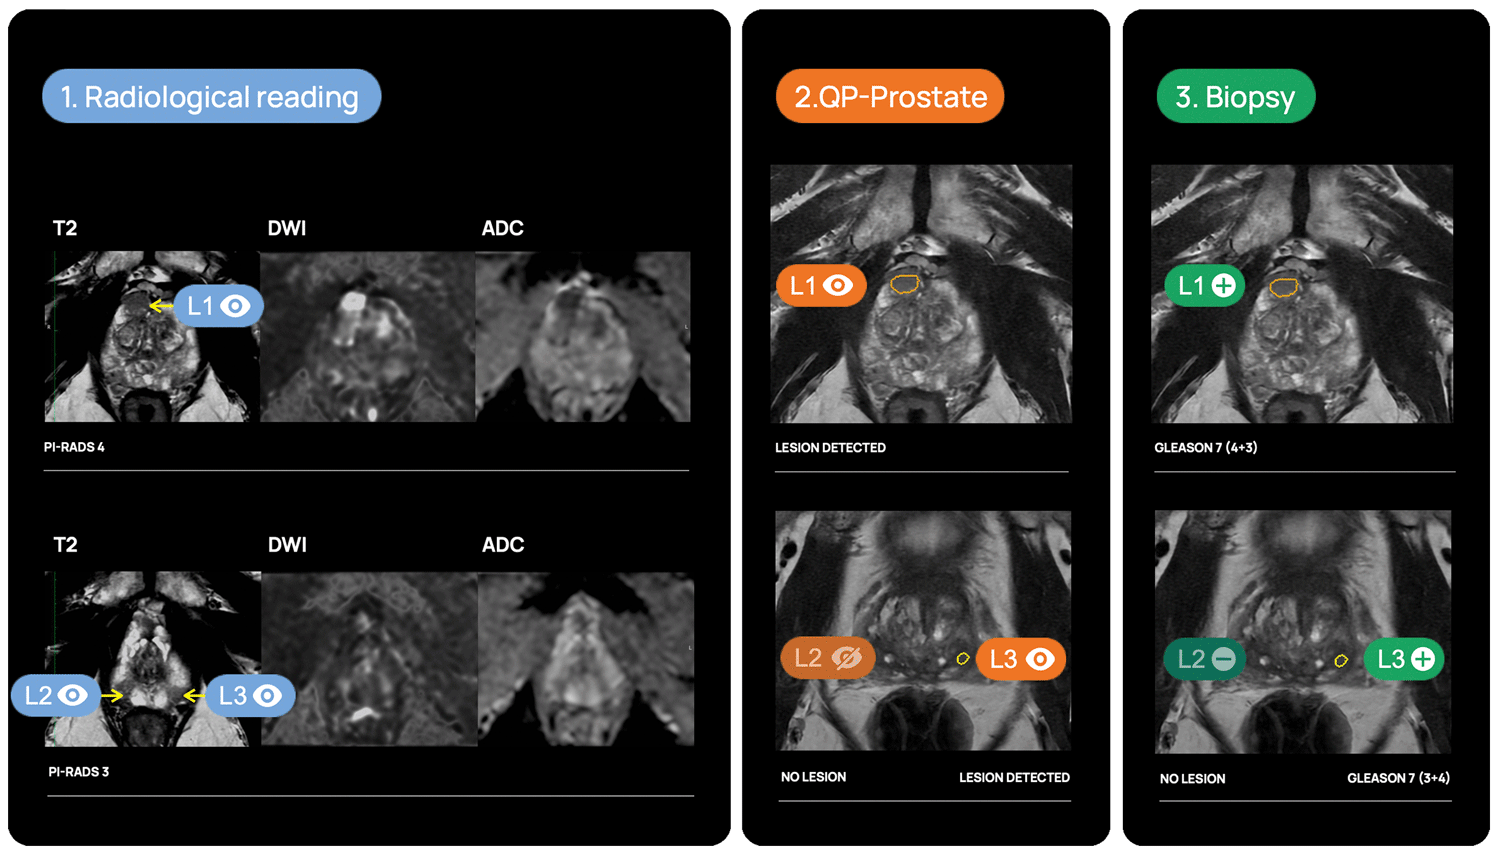

Lesion detection & diagnosis

QP-Prostate automatically identifies and highlights prostate regions suspicious for aggressive prostate cancer, assigning each a confidence-based classification score.

Fusion biopsy planning

QP-Prostate is fully integrated into most of the fusión biopsy devices, to allow a more accurate targeted biopsy.